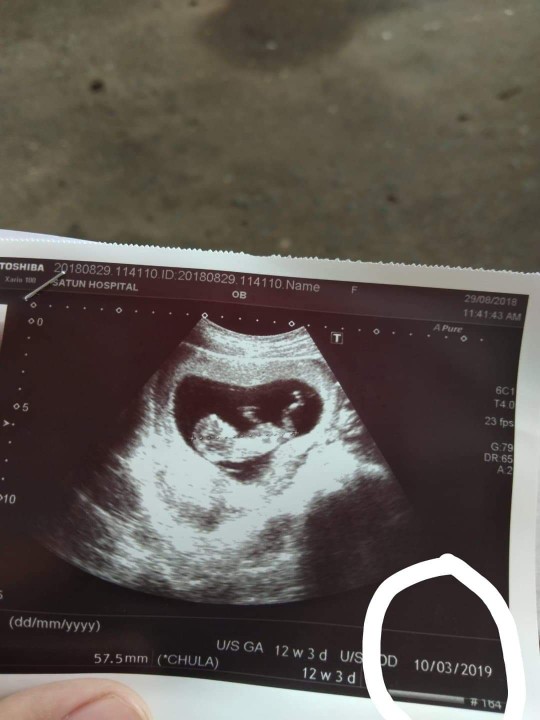

13สัปดา หนูจมูกโด่งไหมค่ะ ❤️❤️❤️🐷👼🏻👼🏻